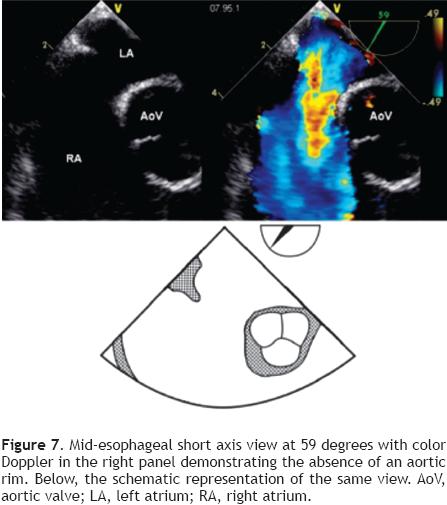

To achieve proper visualization of the Ao (Figure 6), the probe must be at a mid-esophageal level, at 45° with a leftward (counter-clockwise) rotation of the probe to allow simultaneous visualization of the aorta (AA) and the ASD. Sometimes the Ao is very small, or even absent (Figure 7), this finding makes the procedure more challenging but does not, preclude PTC of the defect.